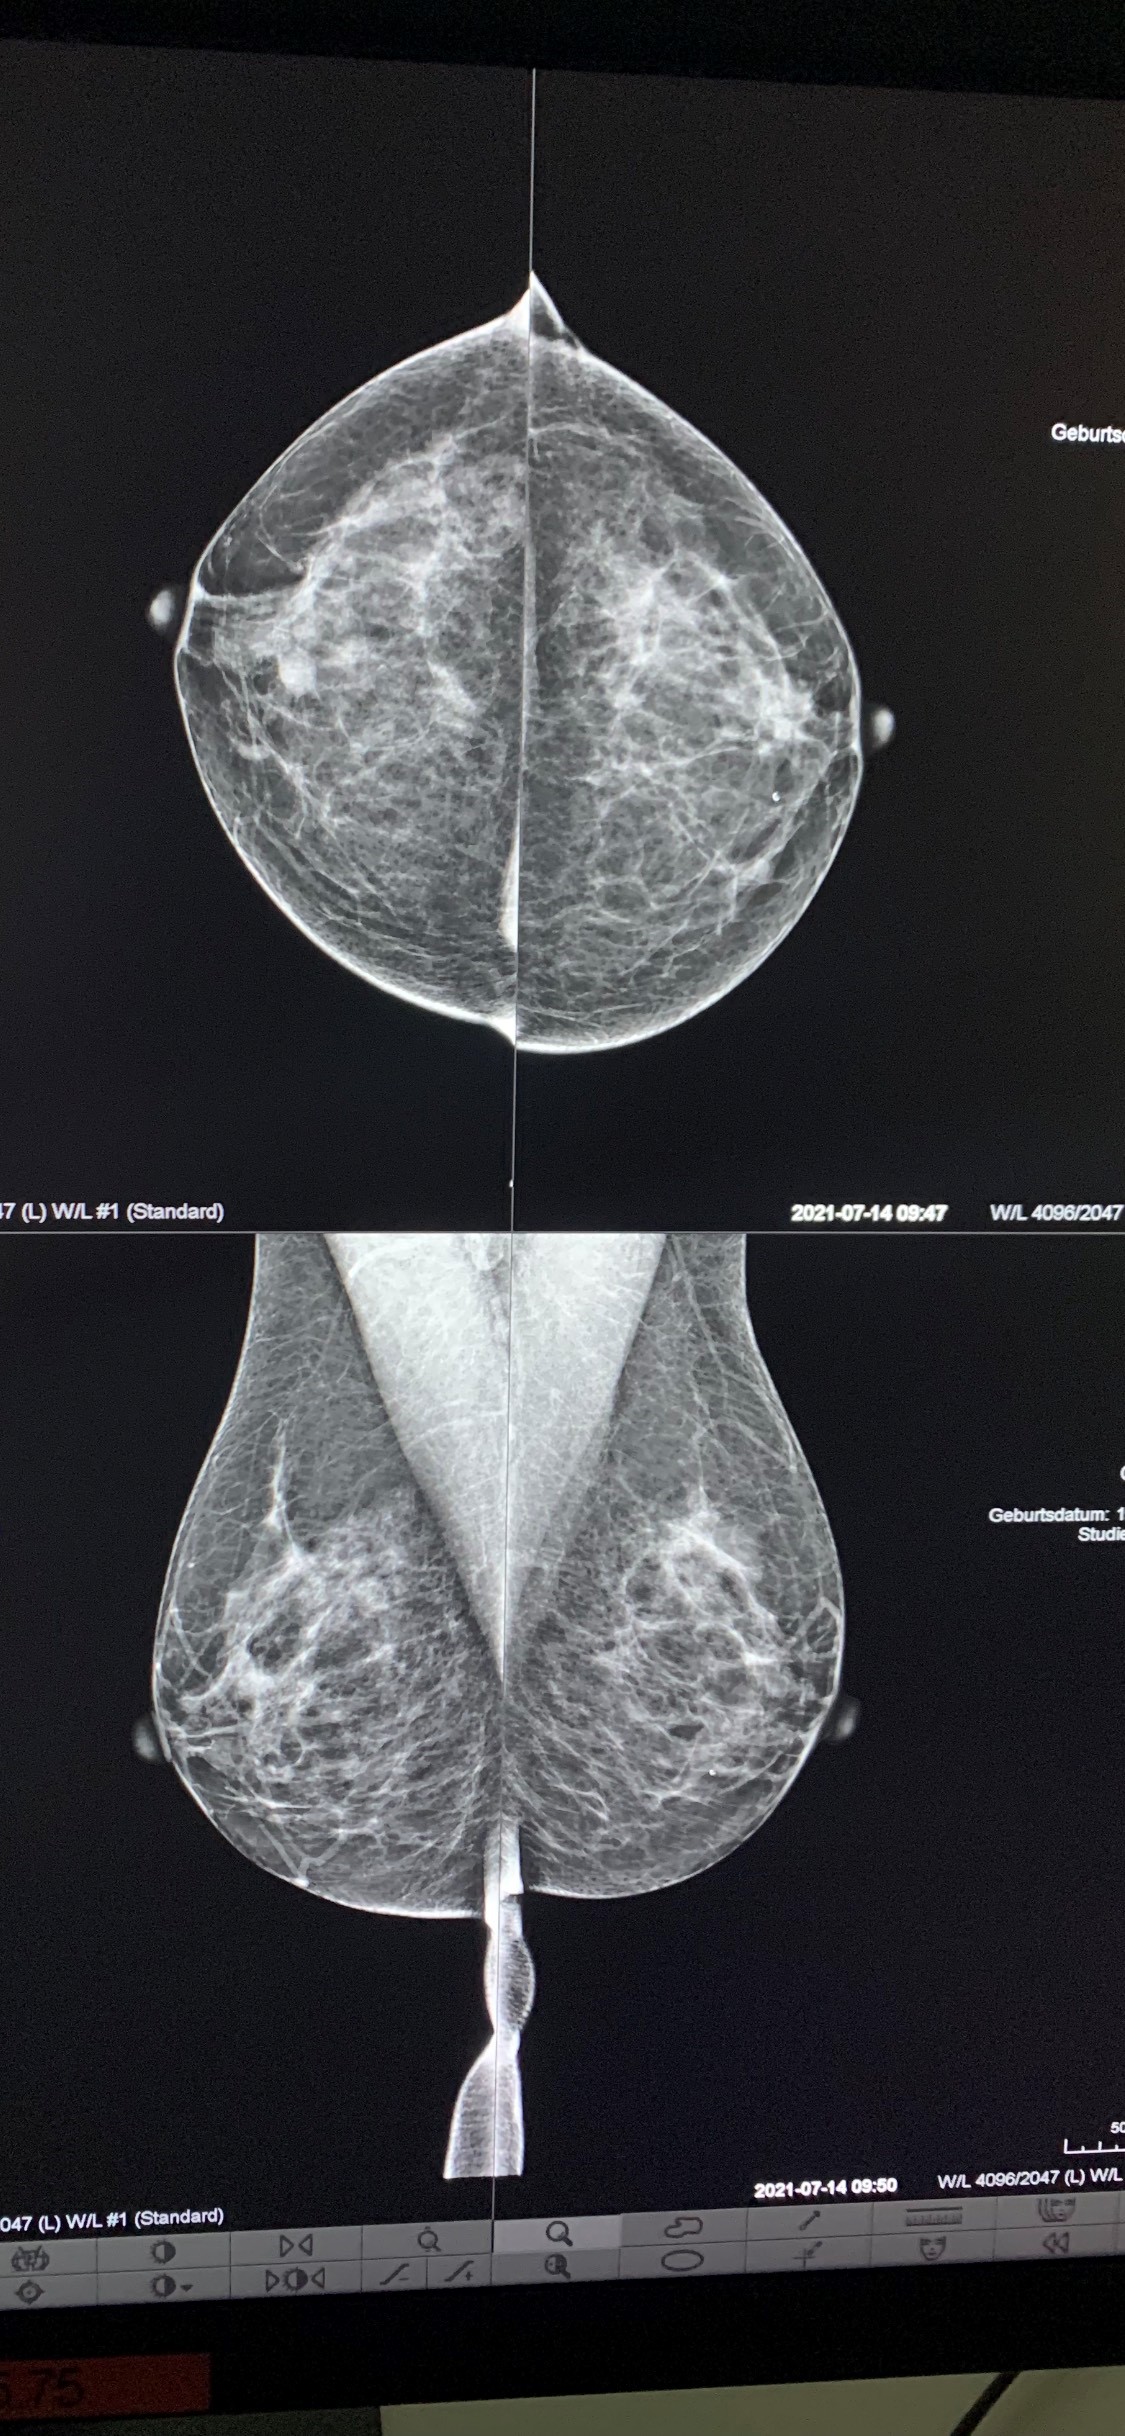

Pamje nga mamografitë